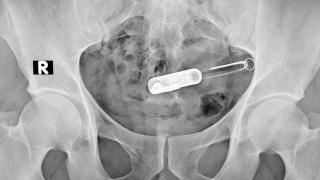

Y no se trata de un miedo infundado, sino que está basado en algunos casos reales. El más grave de ellos es el de una mujer británica, llamada Jeena Paneshar, que terminó con una herida en el cuero cabelludo de 30 centímetros por esta razón. Según explica el periódico Daily Mail, Panesar perdió el control de su coche y chocó contra un árbol dando con su cabeza en el techo de su vehículo. A pesar de ello, la mujer consiguió salir del coche.

Un motorista acabó atendiendo a Panesar, de 19 años, y en el hospital pudieron retirar la pinza que había quedado incrustada después del golpe contra el techo. Pero, además, el complemento le había dejado una herida abierta que recorría su cuero cabelludo, desde la parte trasera del cráneo hasta la ceja izquierda. Este no es, de todas formas, el único caso similar que puede encontrarse en redes sociales como Tik Tok.